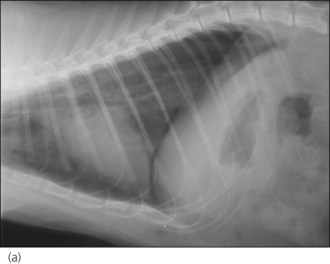

image image

Figure 28.2 (a) Right lateral and (b) dorsoventral thoracic radiographs of a cat showing pneumothorax and pulmonary contusions following trauma.